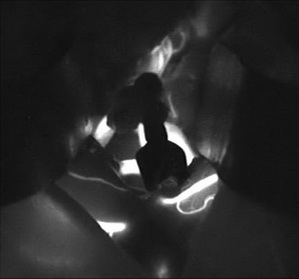

如图所示:原有血管血流清晰,被夹闭动脉瘤不显影

经科室讨论,神经外六科吴杰主任团队为解先生实施了手术,术中将动脉瘤与周围血管准确分离,并成功夹闭。术后复查CT,显示动脉瘤被夹闭,手术区域未见明显异常。